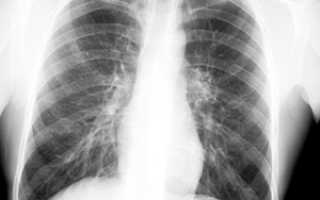

По официальным данным примерно треть населения земного шара тубинфицирована. Но большинство взрослых людей обладает достаточным иммунитетом, чтобы не дать развиться заболеванию. Состояние, когда организм человека инфицирован микобактерией туберкулеза, а болезнь не развивается называется: тубинфицированность. Такое состояние ничем не проявляется. И выявить его можно только с помощью специальных тестов, например, реакции Манту. Но это не означает, что тубинфицированность человеку ничем не грозит.

Настоящий туберкулез, как болезнь с поражением легких, развивается приблизительно у каждого десятого инфицированного. Развитию болезни способствуют: курение, алкоголизм, неправильное питание (особенно голодание), недосыпание, стрессы, малоподвижный образ жизни, недостаточное пребывание на свежем воздухе, хронические заболевания, особенно легких.